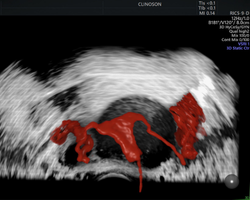

Apaixonado por diagnósticos precisos e tratamentos minimamente invasivos, sou especialista em exames avançados, como a avaliação da endometriose e o HyCoSy (Histerossonografia com Contraste), e também em tratamentos minimamente invasivos de miomas uterinos.

- Pioneiro na realização de HyCoSy – Histerossonossalpingografia com contraste de microbolhas em Porto Alegre

Investigando a infertilidade? Conheça o HyCoSy